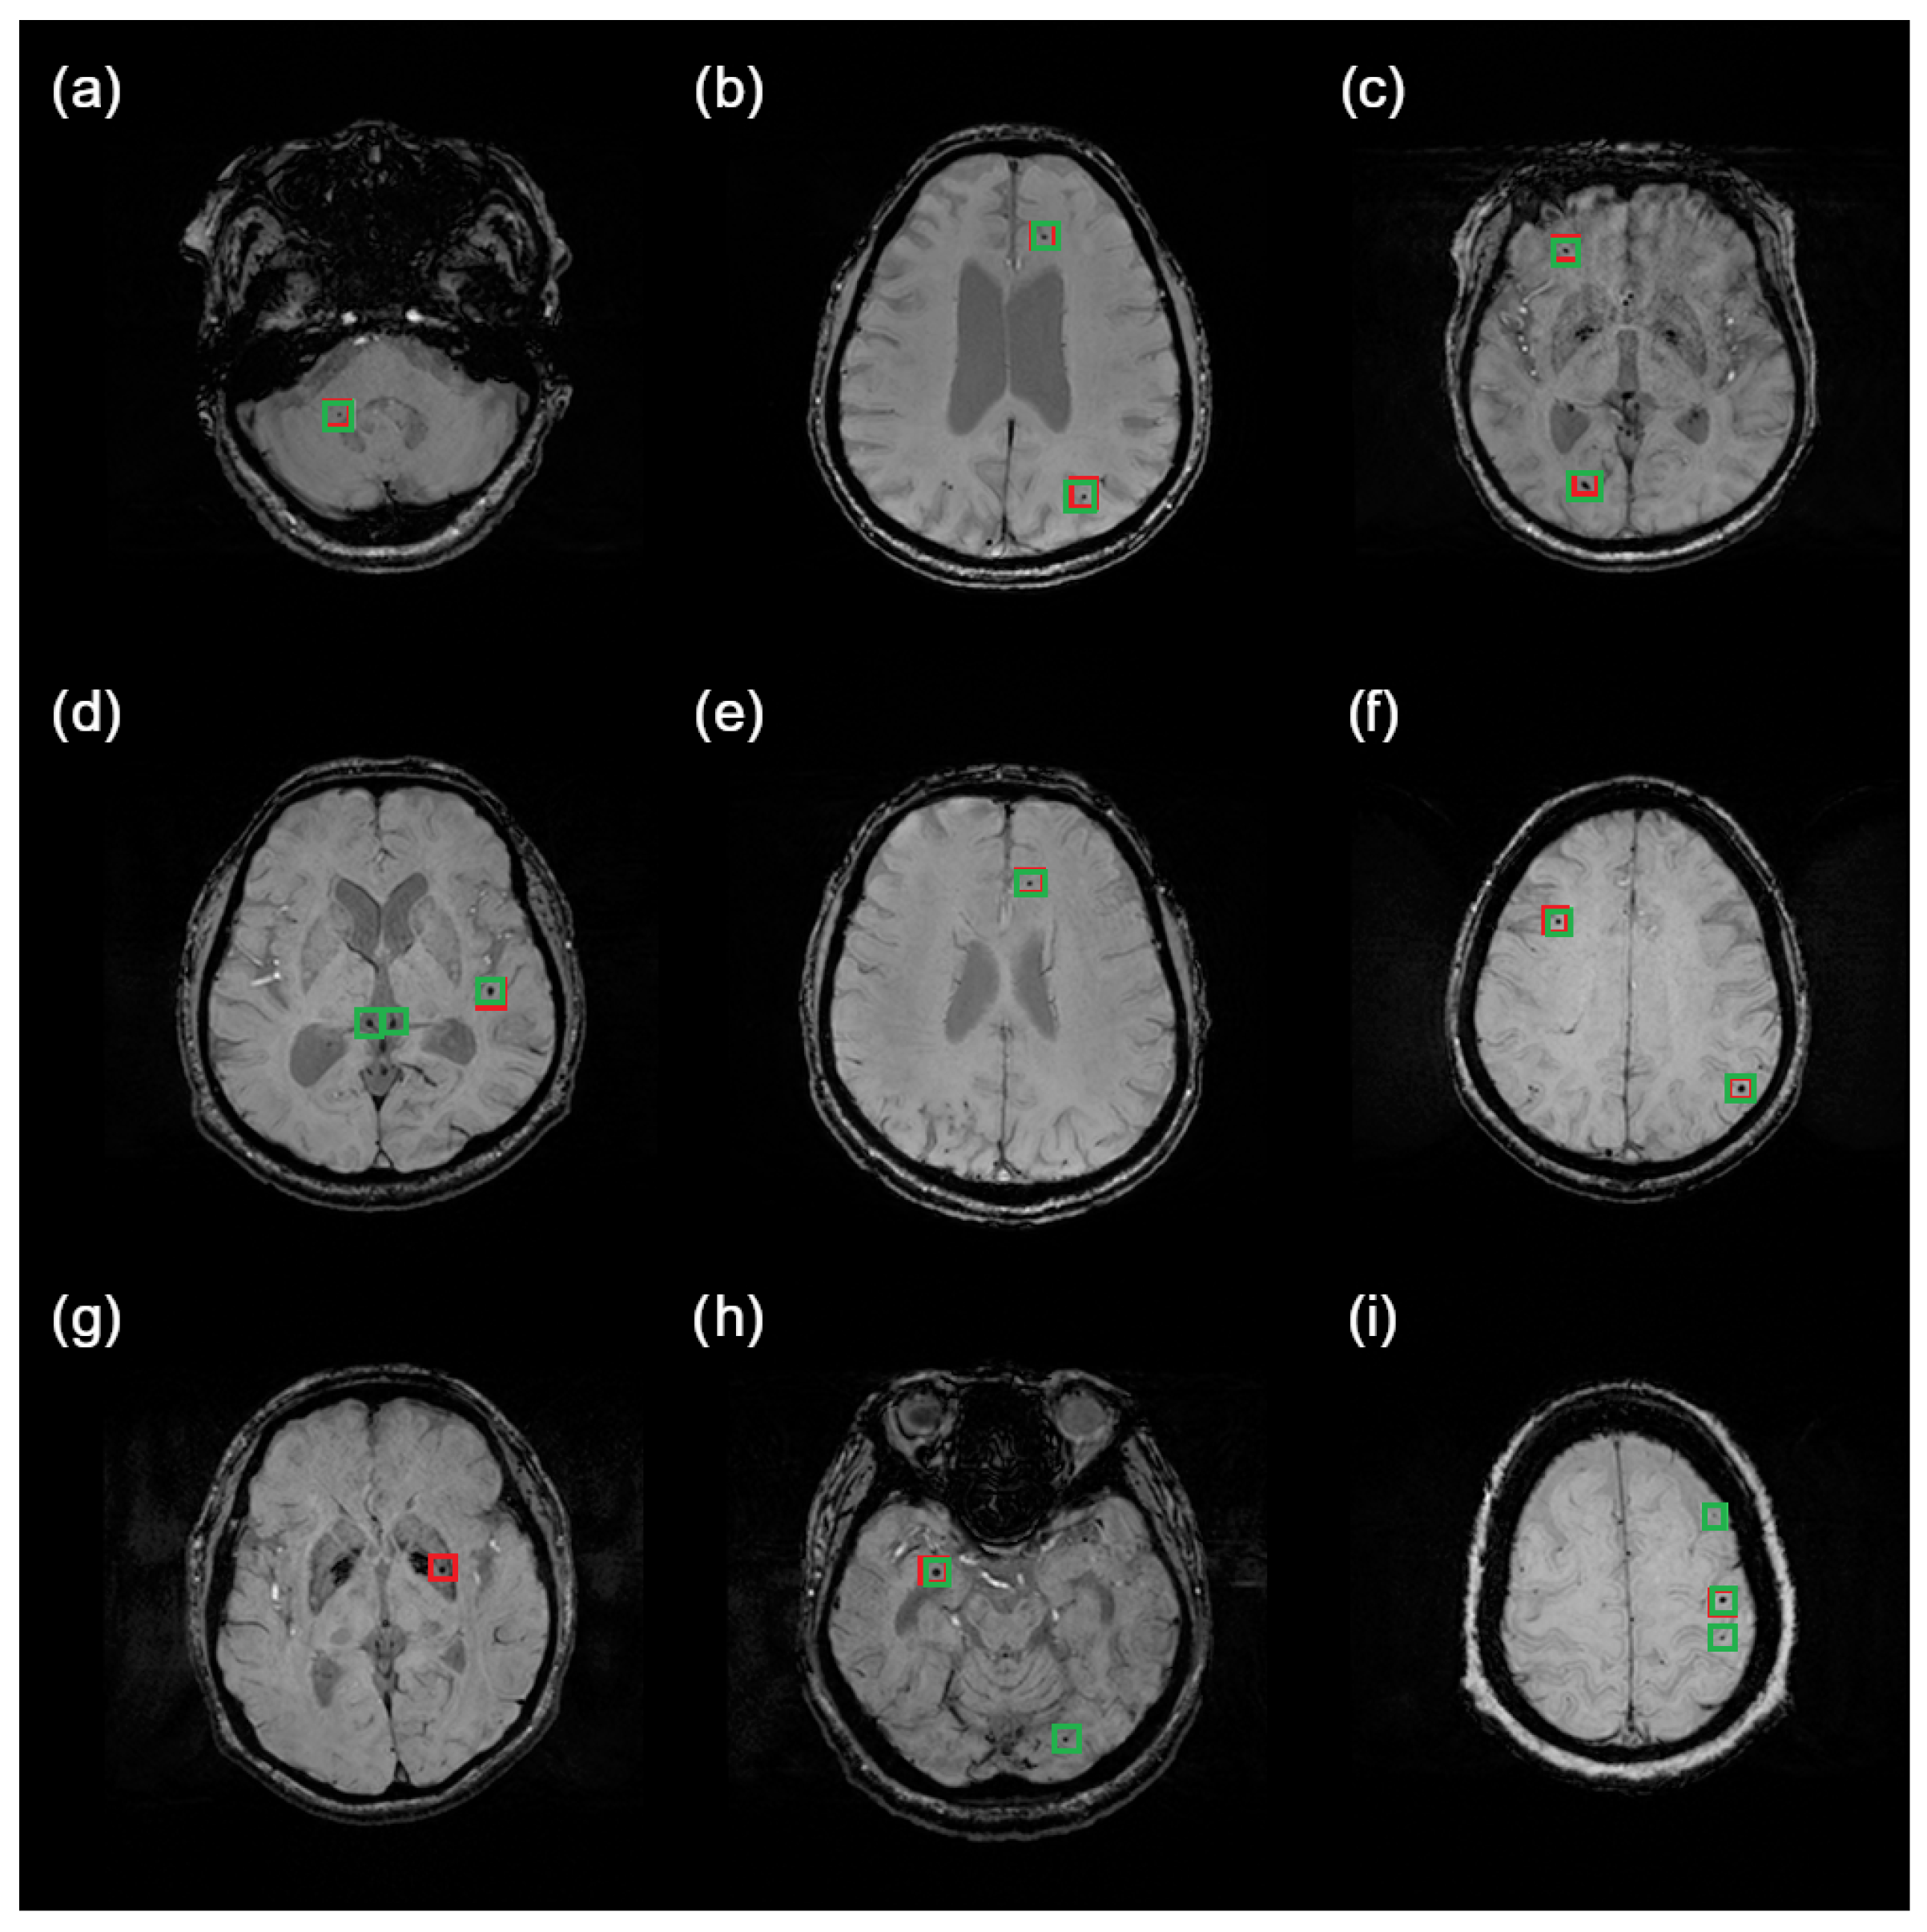

An example of how the system detects a microbleed is illustrated in Figure 6. The red boxes indicate ground truth CMBs, while the green ones represent system predictions. Although cerebral microbleeds are small lesions, the detector manages to find even hardly visible ones. It is also apparent that false-positive predictions are really similar to ground truth CMBs (see Figure 6d, for example).

Figure 6. Samples of results obtained by the proposed system. With red box there are marked Ground truth CMBs are marked with red boxes, while predicted CMBs are marked green. Images were intentionally brightened just for presentation purposes. Examples (ac,e,f) show correct predictions. Examples (d,h,i) show false-positive predictions. Example (g) shows a false-negative prediction.